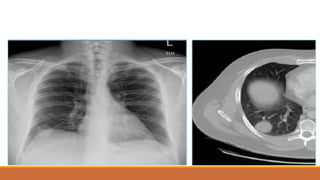

XẸP THÙY TRÊN(P)

XẸP PHỔI DO U

XẸP THÙY GIỮA(P)